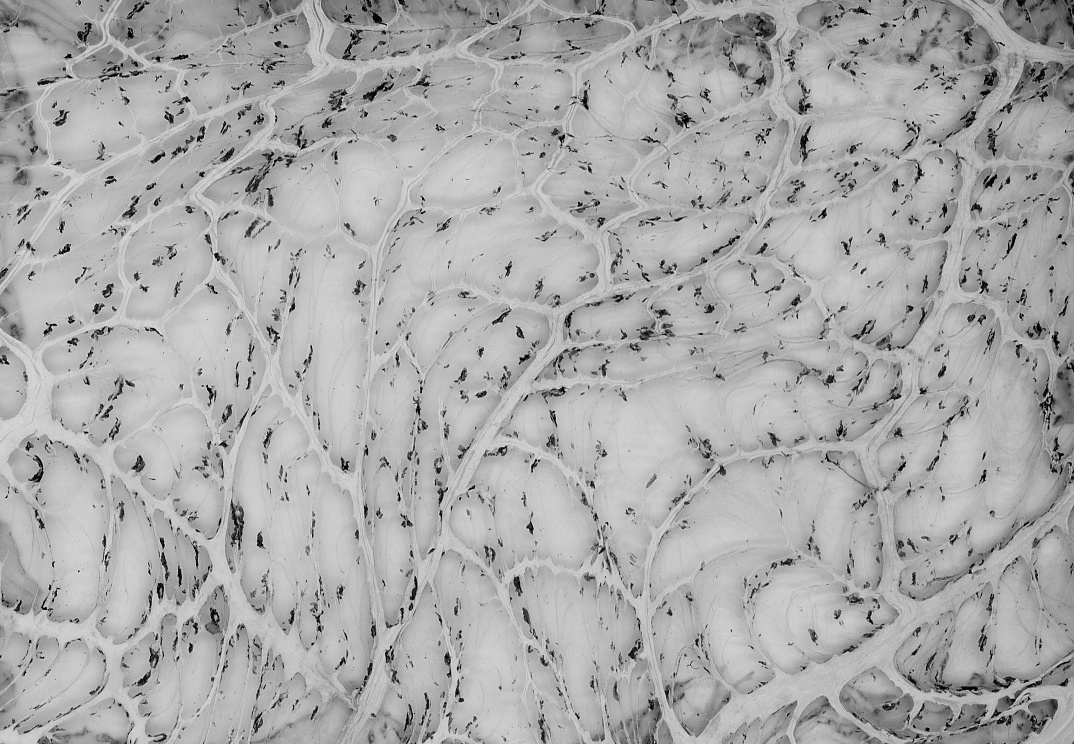

Mule deer : mesentry

Glass slide of the mesentry of a mule deer showing pigment deposition along with chronic F magna infection. Mesentry is a continuous folded band of membranous tissue (peritoneum) that is attached to the wall of the abdomen and encloses the viscera/intestines.

• 1 glass slide : black and white ; 10 x 15 cm